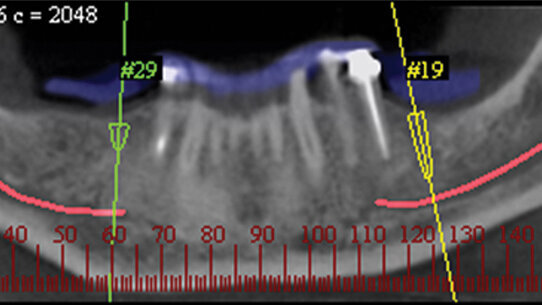

CBCT carries very important radiographic, restorative and surgical information for dental implant planning, taking the guesswork out of what we do, and it is rapidly emerging as the diagnostic imaging standard of care. This information includes implant trajectory, distribution, depth and proximity to critical anatomical landmarks such as the mandibular canal, maxillary sinus, adjacent roots and alveolar cortical plates and undercuts.

About a dozen of these virtual implant planning software solutions are used for general oral implantology treatment strategy, of which only eight are ultimately used to translate the treatment strategy into an actual physical surgical guidance drilling template, thus taking the guesswork out of oral implantology (Figs. 1 & 2).

Utilization of these adjunctive state-of-the-art technologies altered the manner in which we pull together diagnostic data, plan and execute both simple and complex implant cases. These surgical guidance systems offer safer and more predictable placement of dental implants, ensuring accurate transfer of critical restorative and anatomical information to the surgical site.